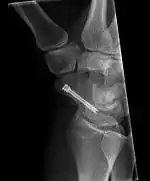

Внаслідок браку кровопостачання до окремих ділянок човноподібної кістки її загоювання йде повільно, тому важливі своєчасні діагностика і лікування (у першу чергу іммобілізація або хірургічна фіксація), що підвищують ймовірність правильного зростання фрагментів[8]. Відсутність належного лікування може призвести до посттравматичного остеоартрозу зап'ястка[5]; почасти цьому сприяє той же брак кровопостачання проксимальної ділянки[6]. Навіть вчасно іммобілізована кістка може вимагати хірургічного лікування (фіксації фрагментів безголовковими гвинтами, наприклад, гвинтом Герберта).